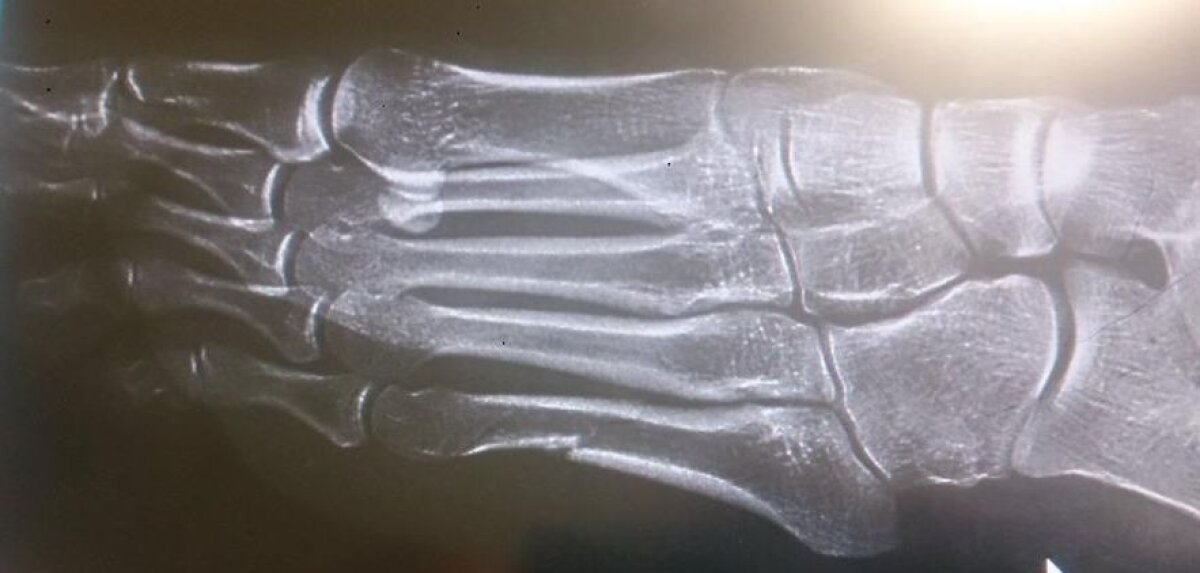

Foto 2/3 : Radiografia piciorului polonezei şi fractura vizibilă